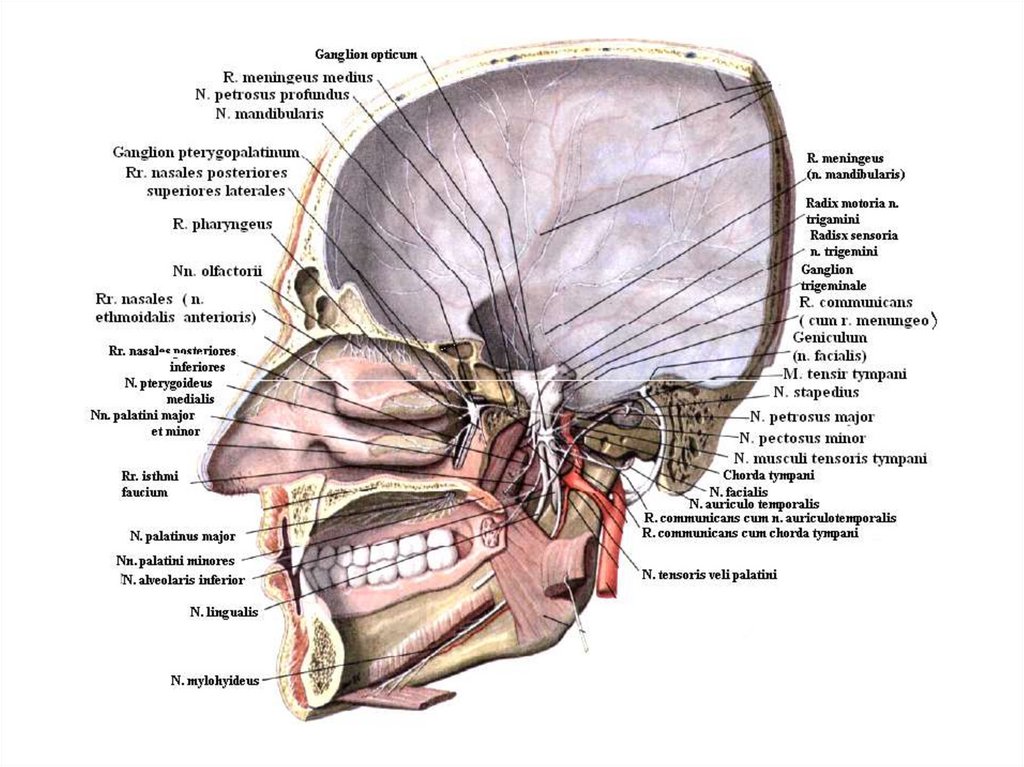

Анатомические изображения срединной сагиттальной линии черепа